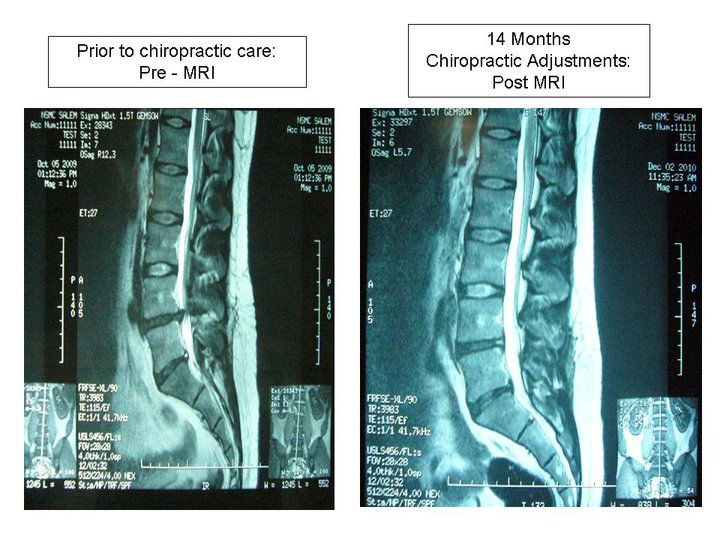

Low Back Pain story worth sharing…this individual works at an MRI center and tracked his own MRI’s to determine his progress under chiropractic care. Notice the L4-L5 disc height before and after specific chiropractic care. Debilitating sciatica resolved, expensive back surgery averted, useless cortisone and facet injections avoided. Let us remember that the body is an amazing self-healing, self-organizing system that needs no help only no interference. Thanks for the testimonial from the patient who followed and tracked his care with undeniable scientific evidence.